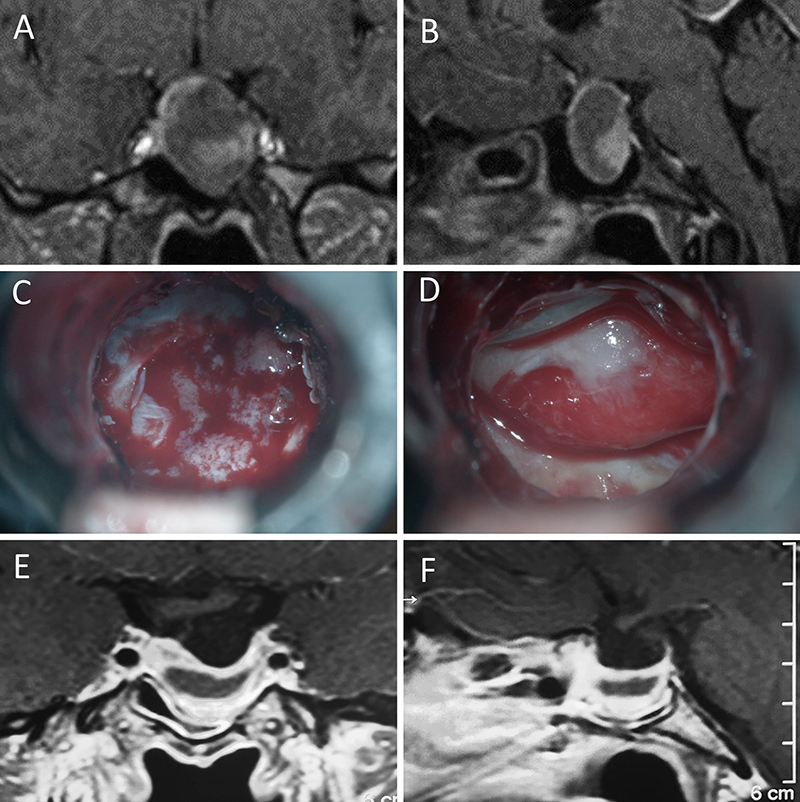

Figura 7: Acromegalia en mujer de 39 años. Con remisión bioquímica tras la cirugía. A-B: RM preoperatoria; C-D: intraoperatorio; E-F: RM postoperatoria.

Figura 8: Acromegalia en mujer de 50 años. Con remisión bioquímica tras la cirugía. A-B: RM preoperatoria; C-D: intraoperatorio; E-F: RM postoperatoria.

Figura 9: Acromegalia en mujer de 54 años. Con remisión bioquímica tras la cirugía. A-B: RM preoperatoria; C-D: intraoperatorio; E-F: RM postoperatoria.

Figura 10: Acromegalia en mujer de 54 años. Se objetivo previo a la cirugía un componente significativo del tumor invadiendo el seno cavernoso derecho. No se logró remisión bioquímica tras la cirugía. A-B: RM preoperatoria; C-D: intraoperatorio; E-F: RM postoperatoria.